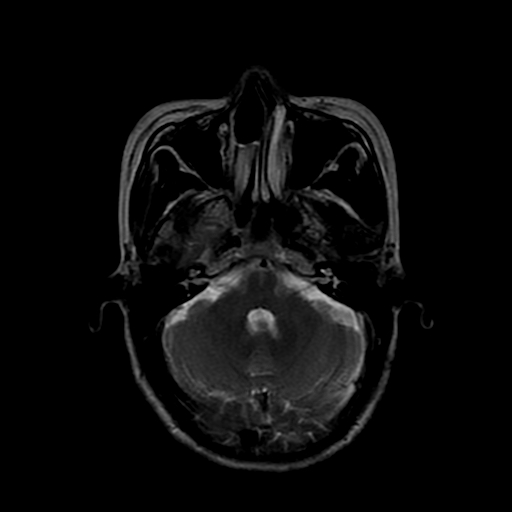

女性,47岁。mri号03027,外伤致头痛9天,抽搐一天,原无类似病史。

颞叶前部萎缩,海马萎缩,t2wi海马高信号,支持海马硬化。

双侧海马区t1低,t2高信号。为什么都考虑硬化?发病原因?鉴别诊断:炎症,梗塞等能一下子除外吗?